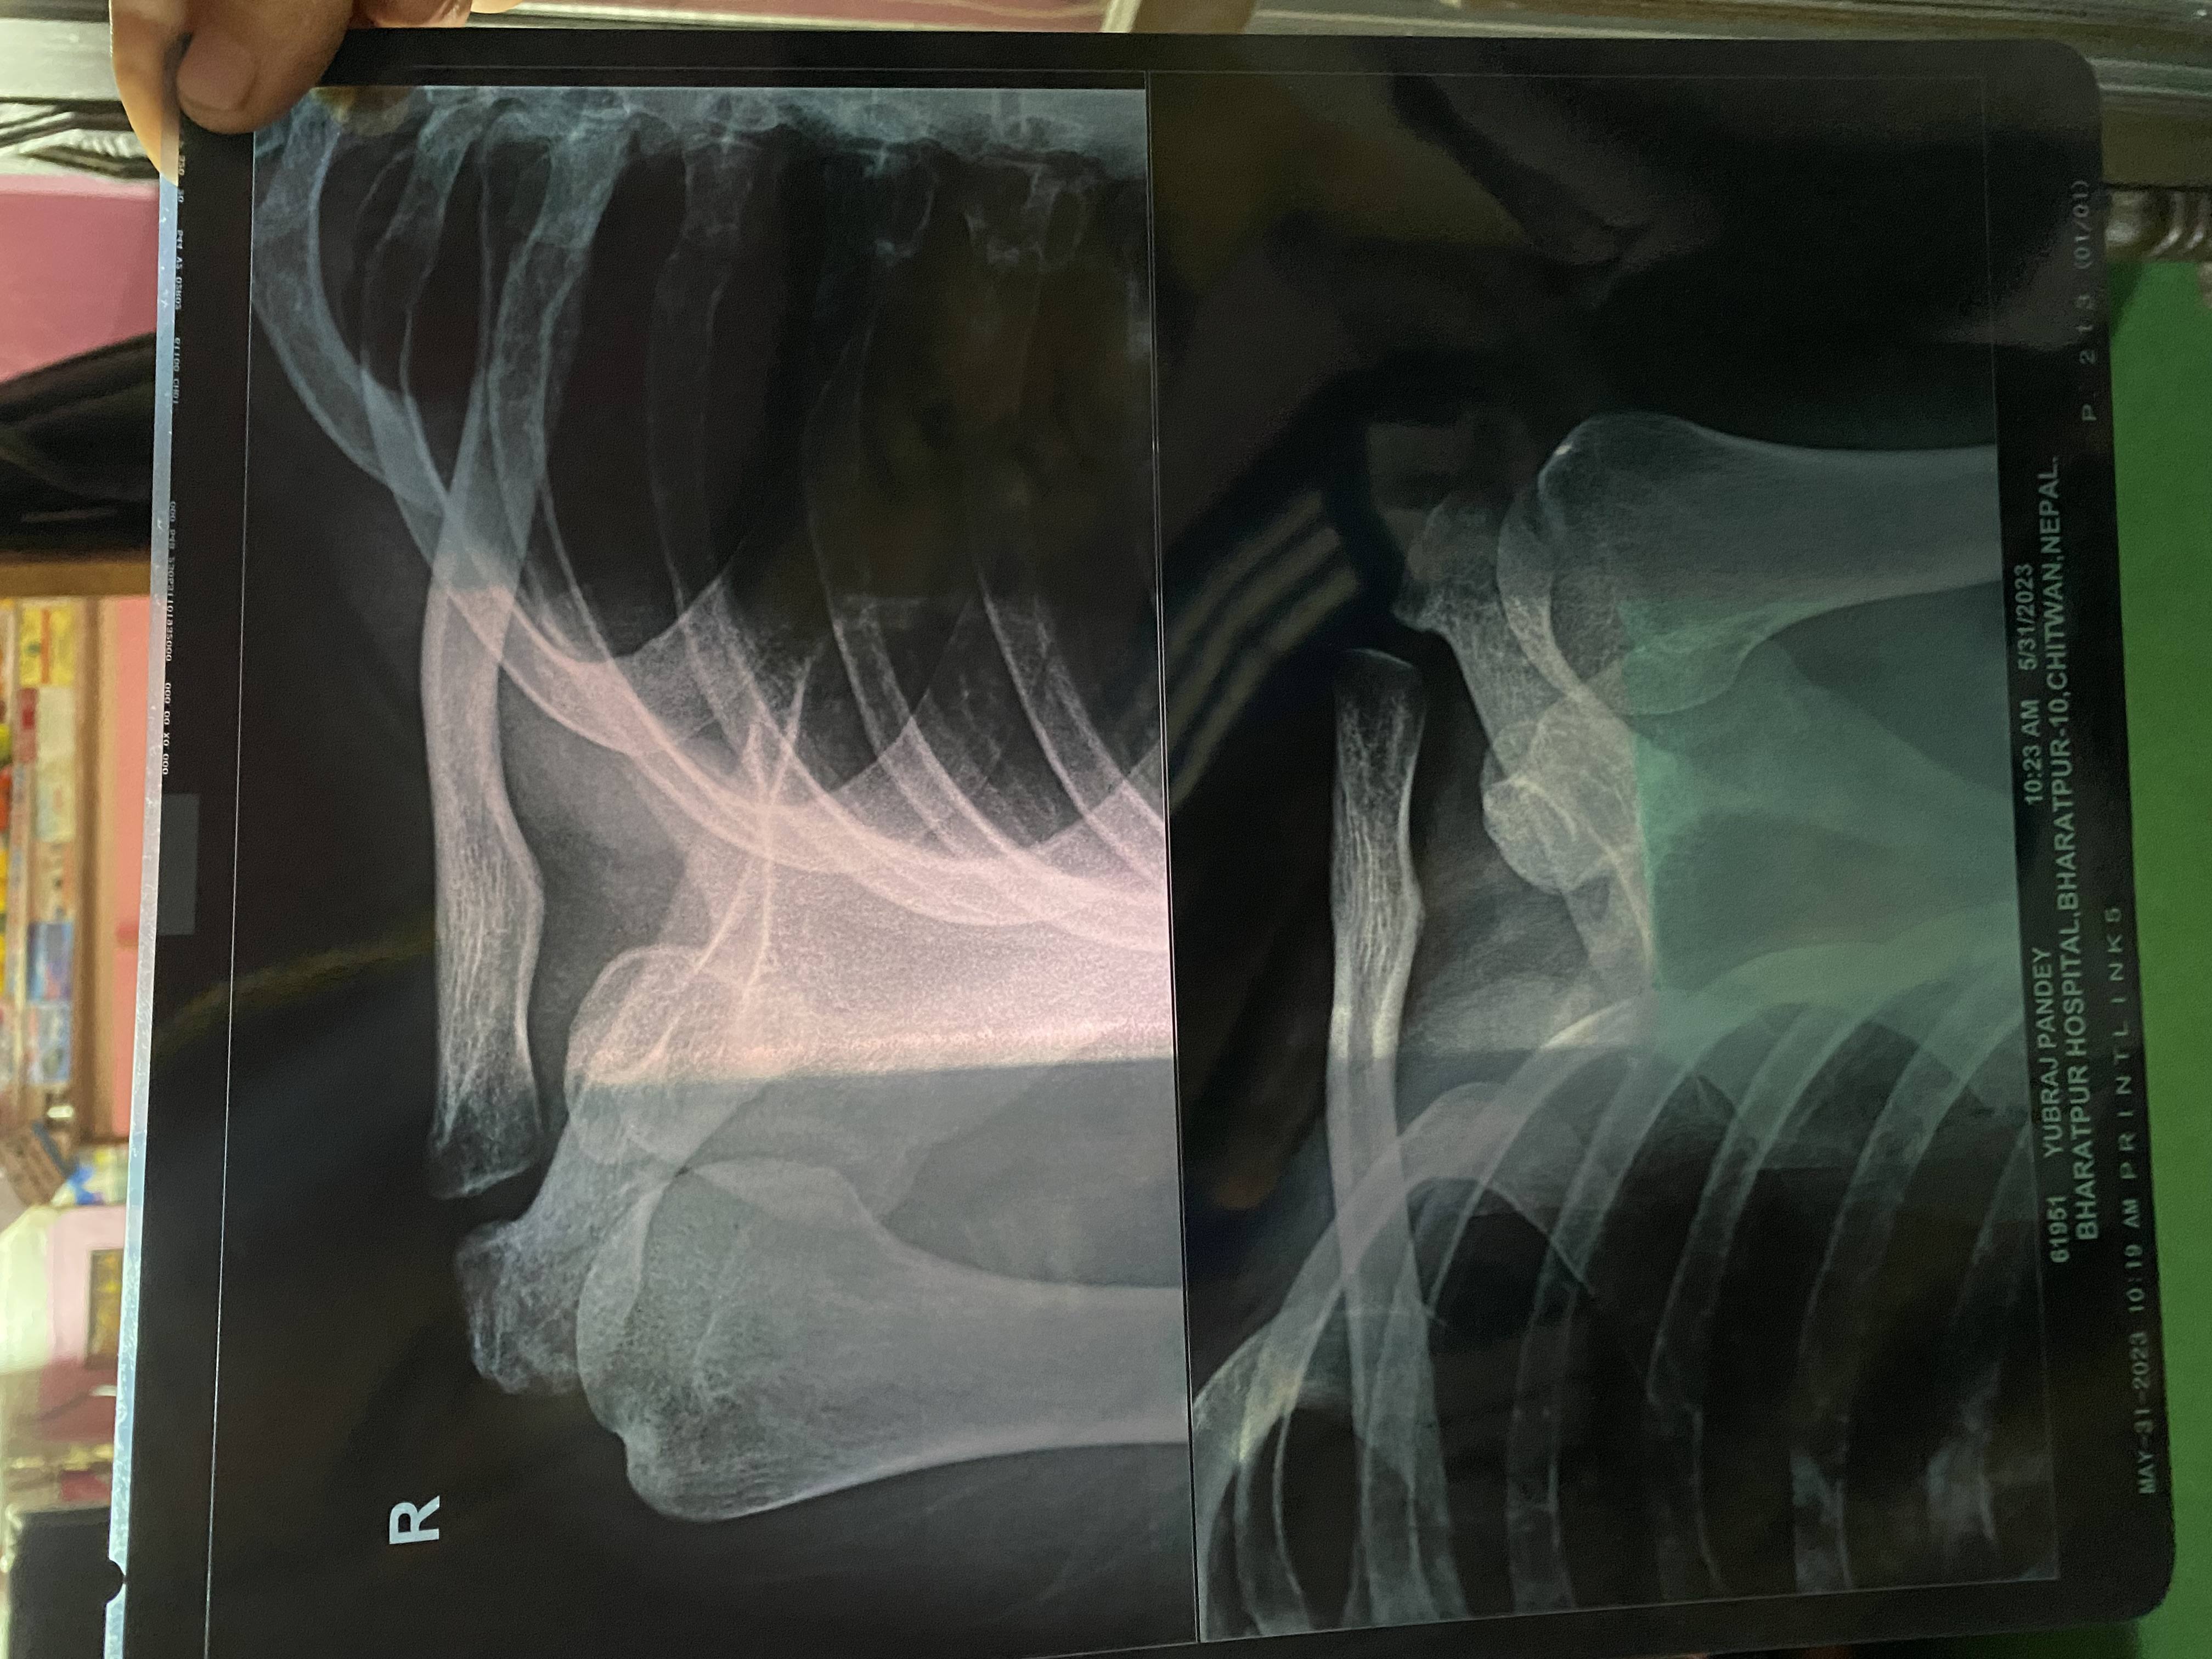

Yubaraj Pandey

I have pain in my left shoulder Can you find out what's the problem ?

Here are x-rays of 2 different dates and inform me after complete

reason of accident (Fallen From Tree)